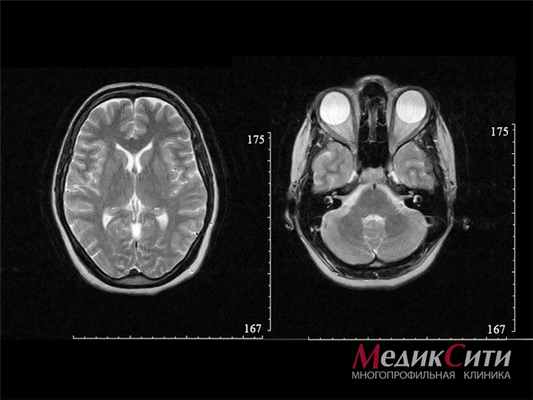

![]()

МРТ головного мозга